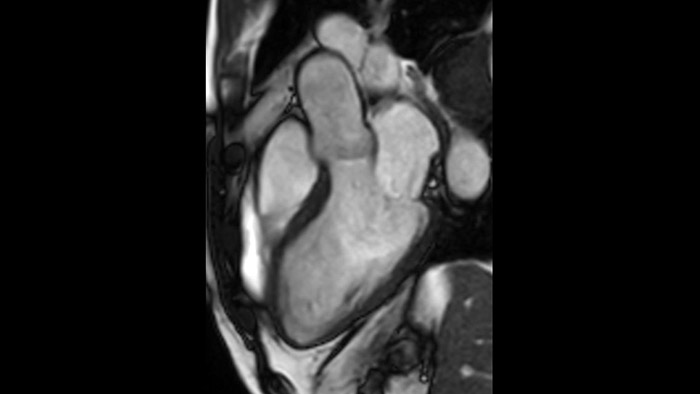

Diagnostic and prognostic utility of cardiac MR is increasing. Assess the anatomy and function of the heart using cine acquisitions, acquire information about perfusion and viability of the cardiac tissue, visualise potential edema with black blood sequence, access and even quantify tissue characterisation with CardiacQuant.

IntelliSpace Portal MR Caas5,6 Strain7 assists in patient diagnosis and monitoring by providing global strain parameters such as global longitudinal strain (GLS), global circumferential strain (GCS), and global radial strain (GRS), using short and long axis MR images, as well as describing the myocardium deformation- such as shortening, thickening, and lengthening during the cardiac cycle.